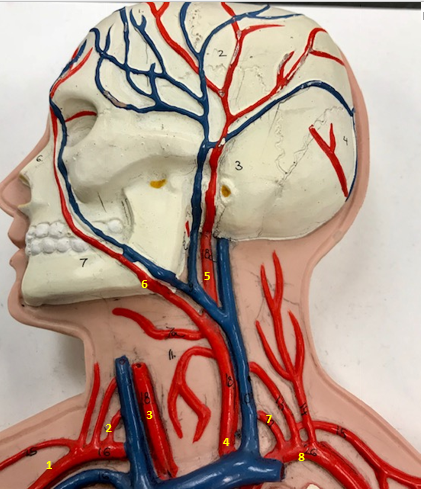

Right subclavian artery

Name #1

Supplies blood to right arm and shoulder

Function of right subclavian artery (1)

Right vertebral artery

Name #2

Supplies blood to brain and spinal cord

Function of right vertebral artery (2)

Right common carotid artery

Name #3

Supplies blood to right neck and head

Function of right common carotid artery (3)

Left common carotid artery

Name #4

Supplies blood to left neck and head

Function of left common carotid artery (4)

Left external carotid artery

Name #5

Supplies blood to face neck and skull

Function left external carotid artery (5)

Left facial artery

Name #6

Supplies blood to face and neck

Function of left facial artery (6)

Left vertebral artery

Name #7

Supplies blood to brain and spinal cord

Function of left vertebral artery (7)

Left subclavian artery

Name #8

Supplies blood to left arm and shoulder

Function of left subclavian artery (8)